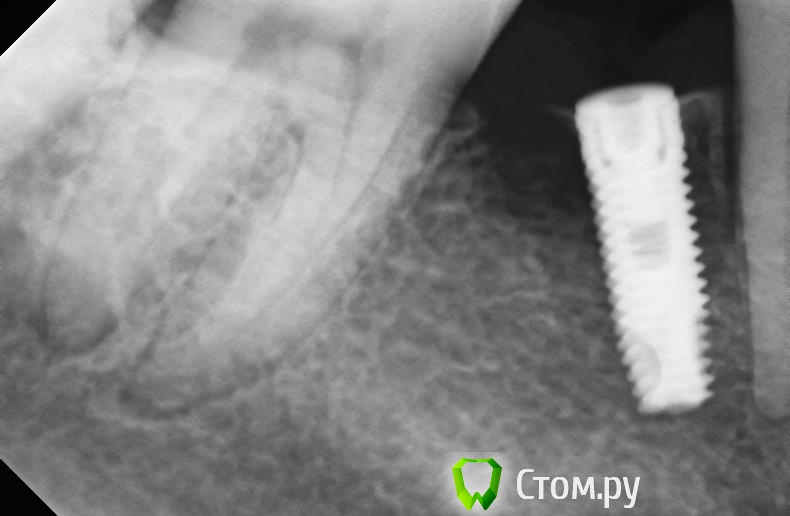

Opimar Опубликовано 10 апреля, 2014 Поделиться Опубликовано 10 апреля, 2014 Всем здравствуйте. Обратился пациент с жалобами на неприятный запах изо рта. На ОРТО вылезло вот это. В полости рта гноетечение из кармана. Подвижности имплантанта нет. Мысли удалить имплантант, откюретажить , оставить на 6 недель и сделать GBR с мембраной или ламиной. Прошу совета. Спасибо. Ссылка на комментарий

Opimar Опубликовано 11 апреля, 2014 Автор Поделиться Опубликовано 11 апреля, 2014 (изменено) Корея? Сколько прошло с момента установки и протезирования? Какова причина, по Вашему мнению? Она самая CSM 4.2 на 10. Ставил не я. Установили 22.11.12 осмотры 4.12.12 и 15.01.13 жалоб нет но там походу и снимков не делали. А вот 5.03.13 в карте запись про наличие разряжения уже на 2/3 длинны. Потом вектром обработали имплантант osteomatrix и мембрана Ace. Ну и естественно толку ноль. 20.05.13 установили коронки. Ну и вчера ко мне пришел. На орто то что наверху выложил. Из причин ну либо перегрев либо гиперкомпрессия наверно. Изменено 11 апреля, 2014 пользователем Opimar Ссылка на комментарий